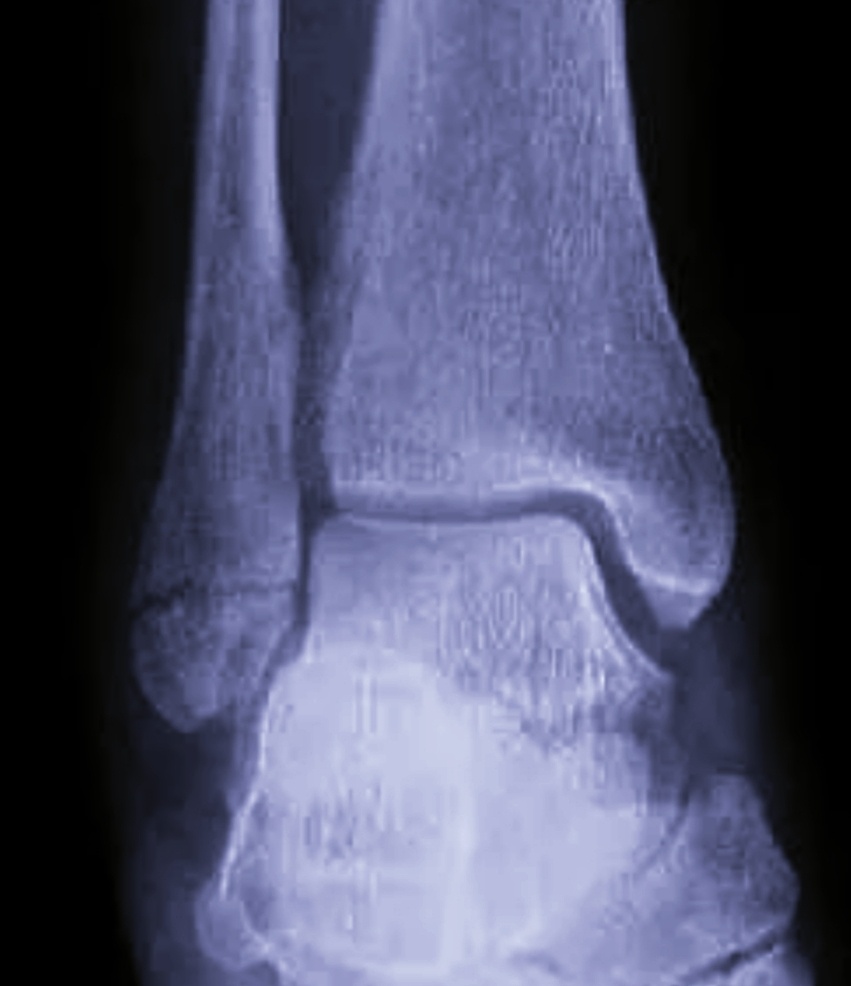

Правый голеностоп назначен.

-На работу пошла , ногу подвернула.

-Да , конечно ,-обращаю я внимание на обувь пациентки на платформе, - немудрено на такой платформе.

–Нет , я была в других ботинках , на каблуке , в тех и подвернула и каблук даже сломала , пришлось вернуться домой , чтобы переобуться, но мне только в этих ботинках удобно более-менее было до вас идти, в других и шагу не могу ступить.

Ну , думаю , раз могла идти , то , может и нет ничего.

Ага , сразу на прямой проекции виден перелом латеральной лодыжки.Вроде , правда без смещения.